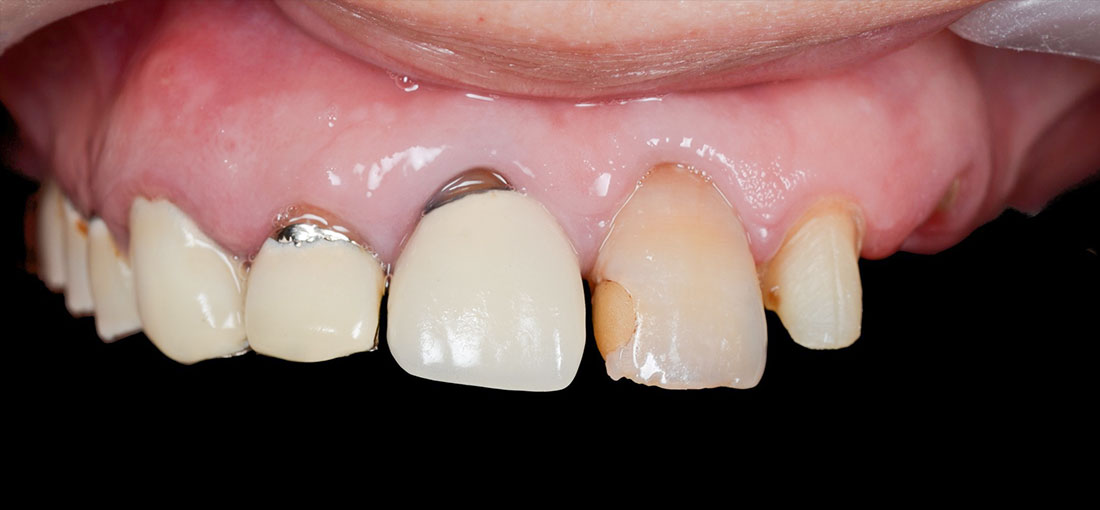

治療内容

ファイバーコアで神経のない歯に土台を作ります。

ファイバーコアは保険治療で使われるメタルコアと異なり白く、被せ物が透けて黒く見えません。

土台になる歯の形を整えて最終的な形の模型を作ります。